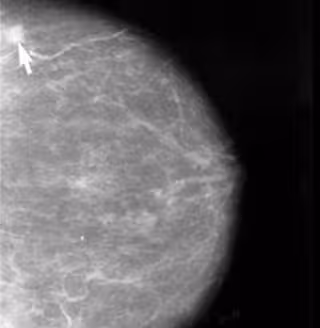

Investigan nueva dianas para tratar un subtipo de cáncer de mama

Foto: UAM